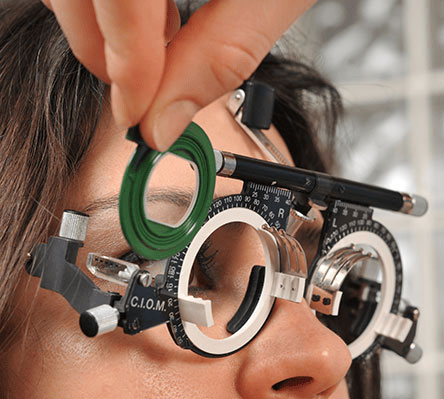

Screening for conditions like glaucoma, cataracts, and macular degeneration.